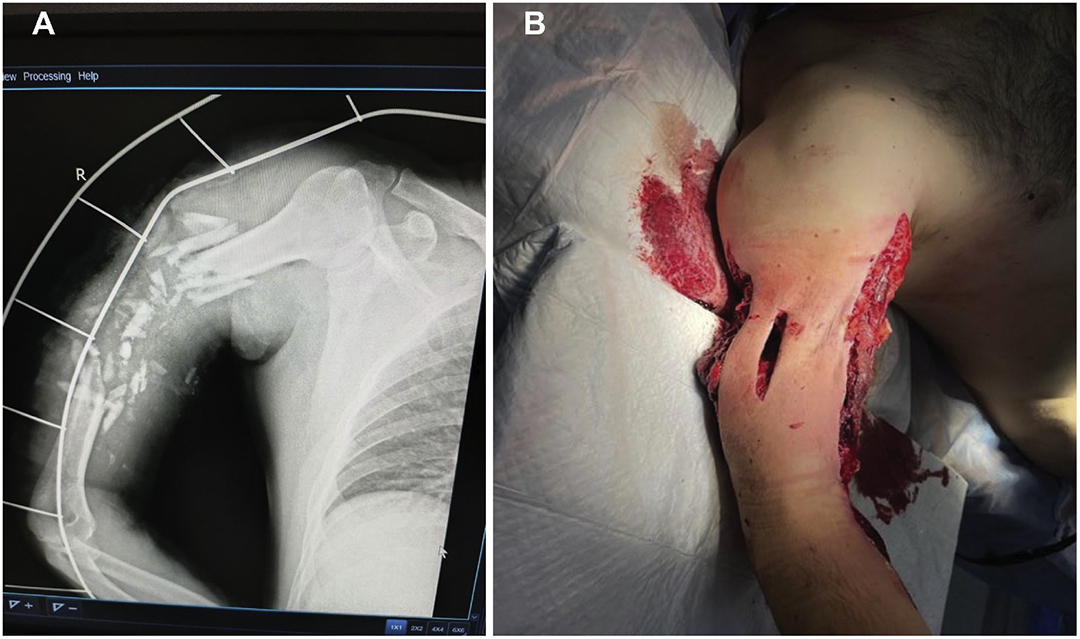

依据 2018 年修订版的 AO/OTA 骨折与脱位分类标准,4 例(占 17%)患者属于单纯性 A 型骨折,8 例(占 33%)为 B 型骨折,12 例(占 50%)为多片段及节段性 C 型骨折。肱骨的多片段严重骨折情况可参考图 1 和图 2。

图 1.右肱骨多碎裂患者的照片,存在骨缺损和碎片移位。伴有骨缺损和碎片移位。A.显示严重骨折的X光片;B.术前照片